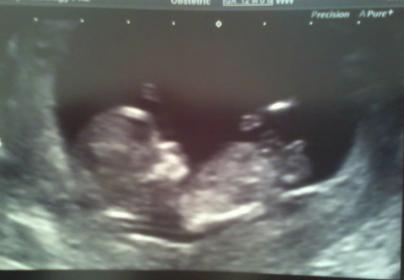

Is this a good nub shot?

This is a 12 week scan of my friend from today and I was wondering if this was a great example of a nub shot. I asked her if she wanted guesses and she said yes please. This pregnancy was a total surprise and I think they were meant to be done so was a bit of a shock. They have G,B,B but the girl is not from her hubby. Thanks heaps :)Attachment 12078

Looks girly to me but what's the actual gestation is it 12 weeks exactly?

Thanks :) 12 weeks exactly. I don't know the nub theory well, will have to find some info on it...